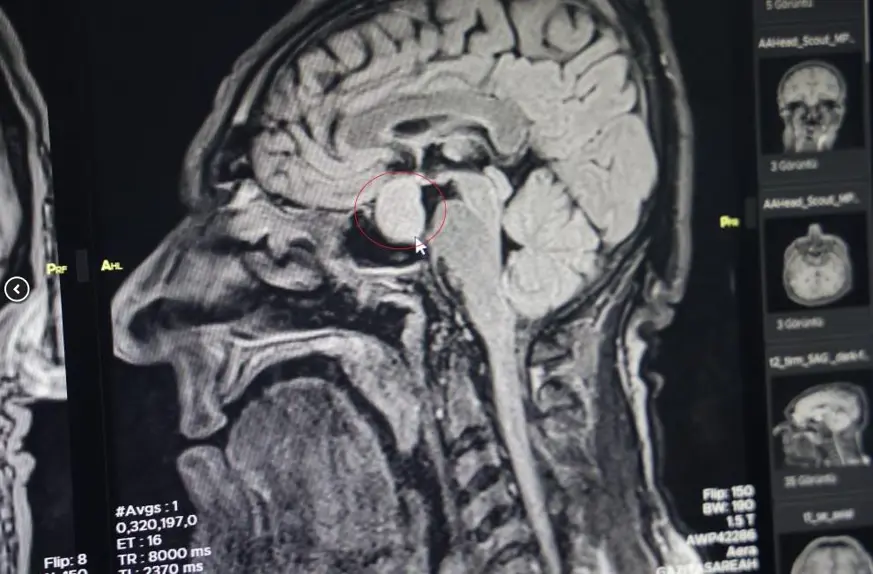

Hastanın dış merkezlerde çekilen MR’larında hipofiz bölgesinde bir iyi huylu tümör tespit edilmesi ve tavsiye üzerine kliniğine başvurduğunu belirten Dr. Çetin, hastanın yatışını yapıp ileri tetkiklerini yaptıklarını kaydetti.

Dr. Çetin, hormonlarına baktıklarında hastanın büyüme hormonları yüksek olduğunu söyleyerek, "Hastayı yapacağımız ameliyat ile ilgili bilgilendirdik. Hastanemizde ilk defa burundan kapalı yöntemle girilerek hipofiz tümörüne müdahale ettik. Allah’a şükür sağ salim bir şekilde, her hangi bir komplikasyon gelişmeden tümörü aldık. İki gün sonra da hastamızı taburcu ettik. Operasyonumuz 2-2,5 saat sürdü. Herhangi bir riskle karşılaşmadık. Hastamızın genel durumu şu an gayet iyi. Kan tetkiklerinde ve hormon düzeyinin de düştüğünü büyük bir memnuniyetle gözlemledik" dedi.

"Kendi açımız ve hastanemiz açısından güzel oldu, gururlandık" diyen Dr. Çetin, "Hipofiz bezinde yetmezlik ve görme sinirlerinde baskı yaptığı zaman görme kaybına neden olabilmektedir. Bu hastamızda ameliyat öncesi görme kaybı bir miktar vardı. Büyüme hormonu oldukça yüksekti. Tümörü boşalttığımız için hormon düzeyi yarıya düştü. 2-3 hafta sonra kontrole gelecek bir daha ölçme imkanı bulacağız. Bu hastalar genelde şimdiye kadar büyükşehirlere gitmekteydiler. Bundan sonra bu tür ameliyatları gerçekleştirme imkanı bulacağız" şeklinde konuştu.